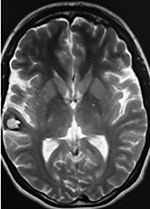

El estudio de RMN presenta una lesión bien circunscrita en hemisferio cerebeloso izquierdo con periferia de predominio hiperintenso en T1 y T2, y centro hipointenso, edema perilesional mínimo, así como una imagen de un vaso venoso alimentador que recorre hacia el ángulo pontocerebeloso izquierdo.

Lesión cerebelosa izquierda ponderaciones en T1 y T2, la flecha señala vaso nutricio hacia el ángulo pontocerebeloso izquierdo, se puede observar el centro de intensidad heterogénea con contenido quístico multiloculado y edema perilesional leve.